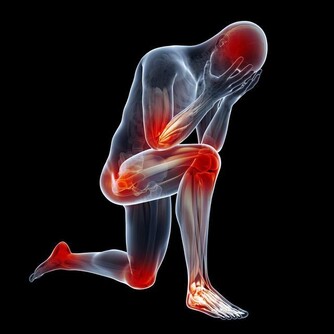

早期老年癡呆有哪些表現?

·記憶衰退,對幾個小時甚至幾分鐘前發生的事都不記得,反复說相同的話、做相同的事;

·無法準確表達自己的意思,所以常被認成嘮叨;

·不能準確判斷物品的位置,容易迷路;

·無法寫出自己想寫的東西,經常詞不達意;

·即使是每天都用到的物品,也無法辨認;

·不會算賬、理解能力差;

·注意力分散、判斷力差;

·性格大變,且多半有狂躁、多疑、抑鬱、妄想、固執;

·行動笨拙,經常做無目的的勞動;